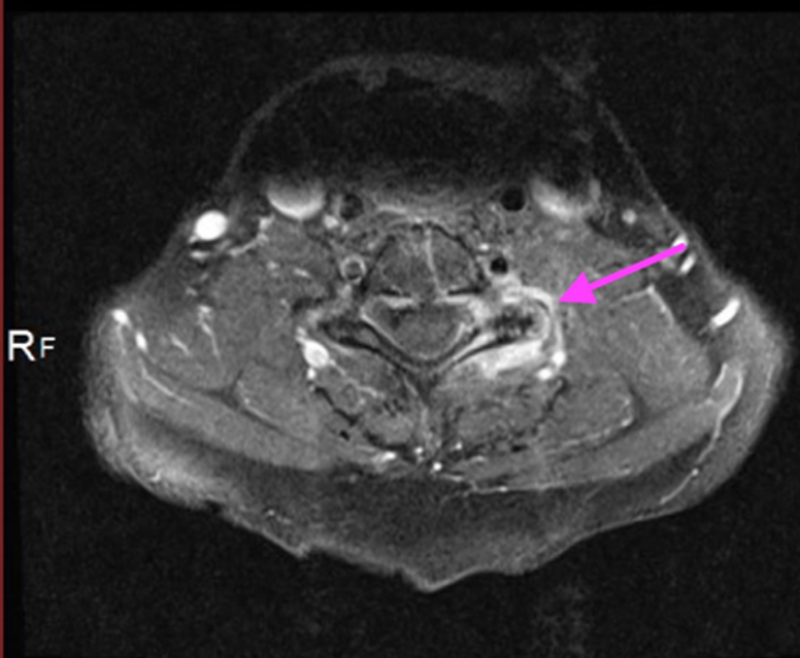

箭头显示在椎间后关节周围和左侧C6/7神经孔内的炎症过程增强

偏振光下正双折射菱形晶体